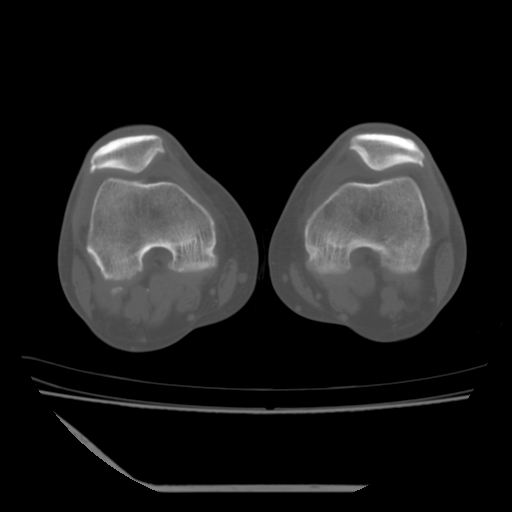

标题: CT13225:老年男性,左膝关节疼痛数月;请各位老师讨论。 [打印本页]

标题: CT13225:老年男性,左膝关节疼痛数月;请各位老师讨论。

骨质增生,骨性关节面硬化,关节积液,考虑退行性骨关节病

关节腔内少量积液,关节面退变。

双膝退变

骨质增生,骨性关节面硬化,关节间隙失常,关节积液,考虑退行性骨关节病.

这个病例诊断:退行性骨关节炎